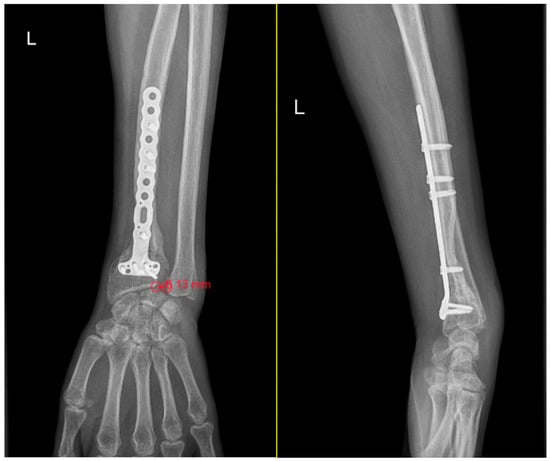

Additional functional measures were recorded to provide a more complete understanding of wrist and forearm performance. Grip strength was compared with the contralateral limb as an objective indicator of functional impairment [22]. Pronation and supination ranges were documented to assess the impact of instability on forearm mobility (Figure 3) [20,23,24]. Pain intensity was quantified using the Visual Analog Scale, with patients rating their symptoms from 0 to 10 [25,26]. These complementary parameters contributed to a broader clinical context for interpreting the severity of DRUJ dysfunction.

Figure 3.

Limited supination in a patient with an initial grade 3 DRUJ injury, and normal pronation clinical aspect at 3 months postoperative.